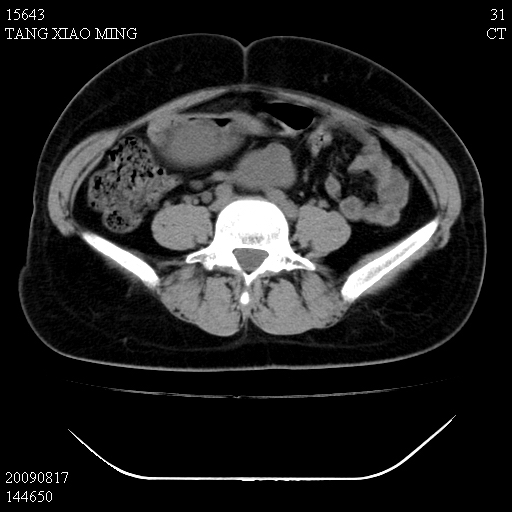

标题: CT21692:盆腔病变

女,33岁,右下腹痛2年余,既往宫外孕病史,如在我院手术,结果下周公布,

可能的诊断。1子宫内膜异位【子宫腺肌症并右卵巢巧克力囊肿】;2 右卵巢囊腺瘤。子宫肌瘤

1)考虑卵巢巧克力囊肿,不排除卵巢囊腺瘤。2)子宫肌瘤可能。

卵巢囊腺瘤,子宫肌瘤,直肠壁厚,不除外占位.